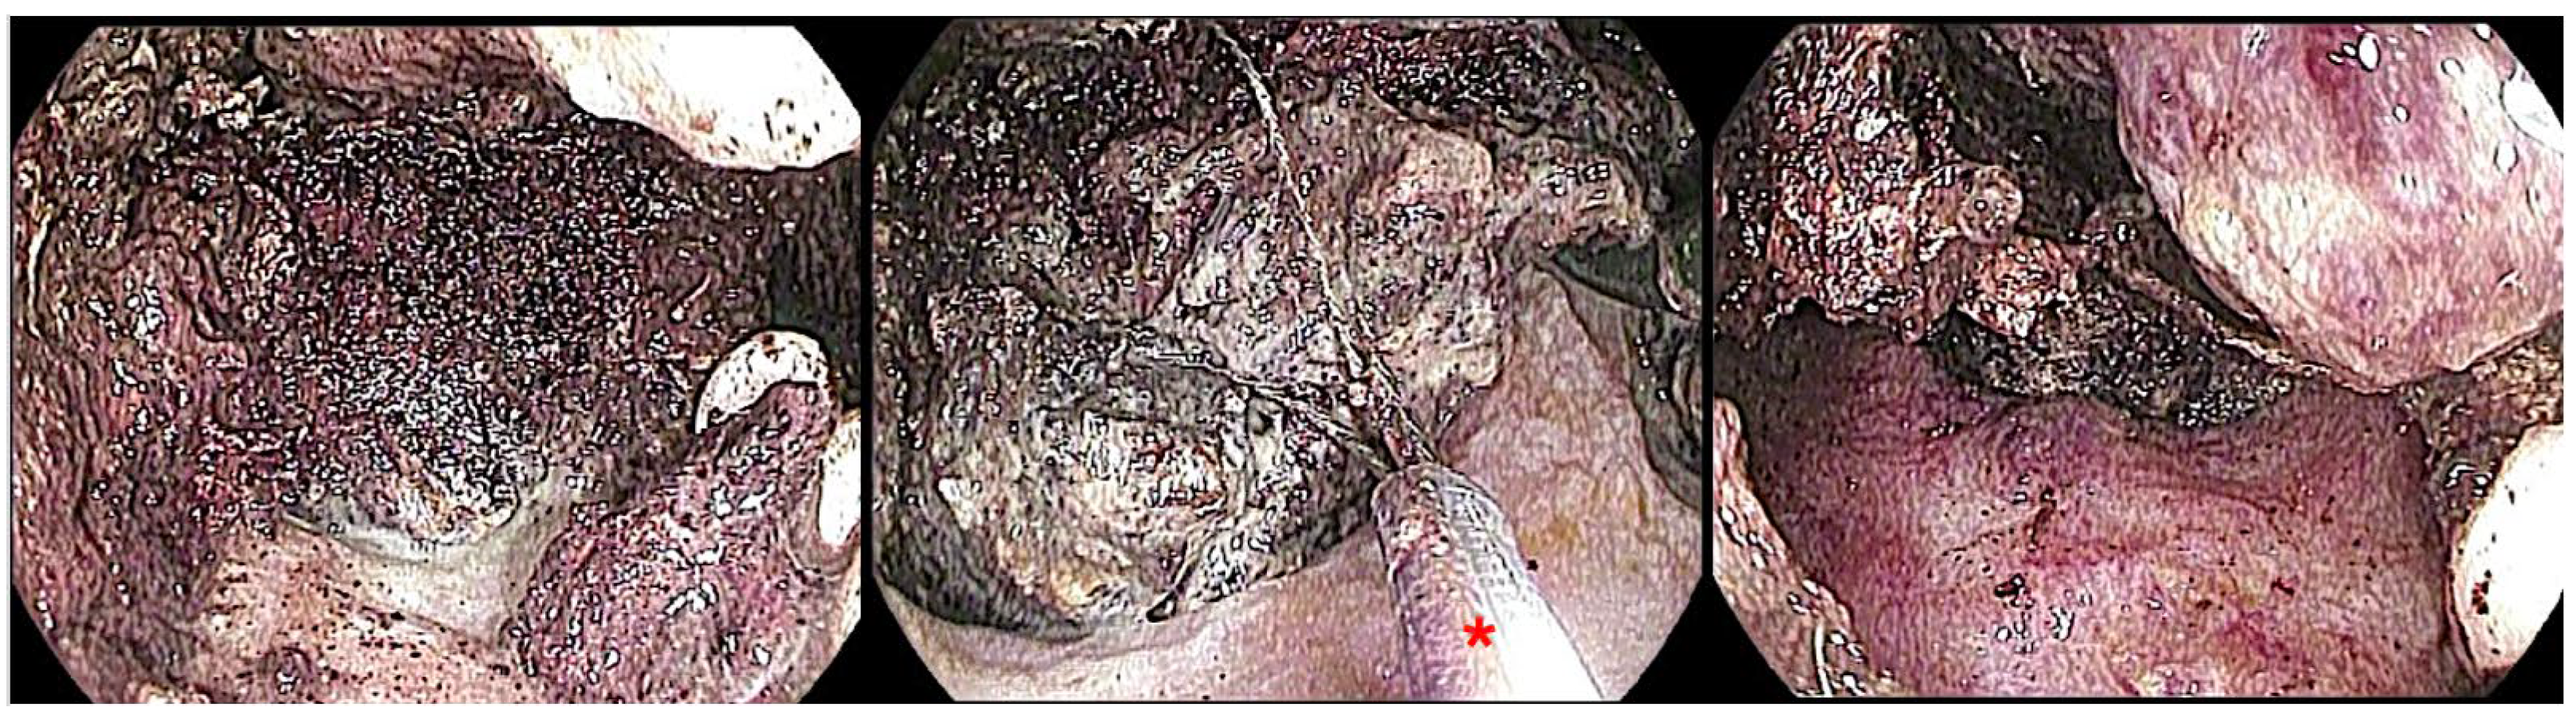

5.2.3. Endoscopic Necrosectomy for WON

Direct Endoscopic Necrosectomy (DEN) Techniques

Step-Up Approach vs. Primary Necrosectomy

Safety Outcomes and Complications